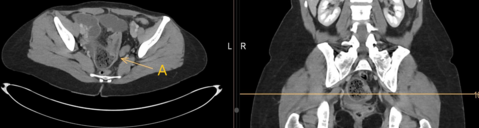

Given the patient's unexplained symptoms, an abdominal CT scan was performed:

The CT scan together with the clinical symptoms confirmed the suspicion of a symptomatic aortic aneurysm necessitating immediate intervention. There was suspicion on the CT scan for an aorto-duodenal fistula. The surgical procedure performed, was an open replacement of the aorta due to the juxtarenal location of the aneurysm and the suspected presence of an aorto-duodenal fistula. A vascular surgeon, assisted by a visceral surgeon, performed the surgery. During the surgery, no evidence of an aorto-duodenal fistula was identified, leading to the decision to replace the juxtarenal aorta with a Dacron interposition Graft. Due to positive blood culture results in the perioperative period, the patient received a long-term course of antibiotic treatment. The patient, who made nonetheless a satisfactory recovery and was discharged two weeks following the surgery, rejected our suggestion of a re-laparotomy for more radical aneurysmal sac debridement and omentoplasty given the high suspicion of a mycotic aneurysm. A PET-CT scan performed six months after the surgery, revealed a graft infection. Despite this finding, the patient expressed unwillingness to undergo further surgical intervention. At the time of publication, the patient is still alive under suppressive antibiotic regimen.

In this case, making the correct diagnosis was a challenge given the stable aneurysm dimensions in comparison to the previous imaging and due to the atypical clinical presentation. The suspicion of an aorto-duodenal fistula on CT scan prompted an open surgical approach. Due to the unfavorable anatomy for an EVAR, due to the very short infrarenal aortic neck, the possible strategy of a bridging procedure was not an option.